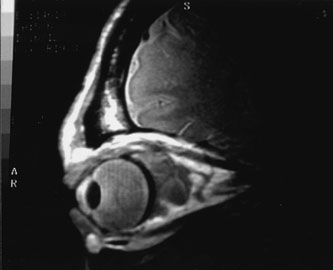

Investigations

If NFM is suspected, MRI should be ordered of the orbits and brain to exclude noncontiguous intracranial anomalies.93 Magnetic resonance imaging demonstrates the dilated cystic spaces with either a hypointense (lymphatic cyst) or hyperintense (hemorrhagic cyst) signal on T1-weighted images, and a hyperintense signal on T2-weighted images (Fig. 10, A&B).94Layering may be seen within the cysts if there has been a recent hemorrhage leaving unresorbed blood. The CT scans of patients with a deep NFM show low-density, poorly defined masses behind the orbital septum in the extraconal and intraconal spaces, which may indent the globe.3 Calcification within the mass (Fig. 11) and inhomogeneous enhancement of the rim and focal areas within the lesion may be seen that corresponds to abnormal endothelially lined channels.3 Enlargement of the bony orbit can occur, particularly with combined lesions.3,89 If the diagnosis is still unclear, ultrasonography can be performed. A cystic orbital mass is seen on B-scan. A-scan shows features of a solid, cellular tumor: low reflectivity, regular homogeneous internal structure, and marked sound attenuation through the mass.3,89 Standard pulsed Doppler ultrasound confirms no intrinsic flow within the lesions.

Fig. 10. A and B. No flow malformation of the orbit. Sagittal magnetic resonance imaging showing dilated cystic spaces hypointense to muscle on T1-weighted images (A) and hyperintense to muscle on T2-weighted images (B).